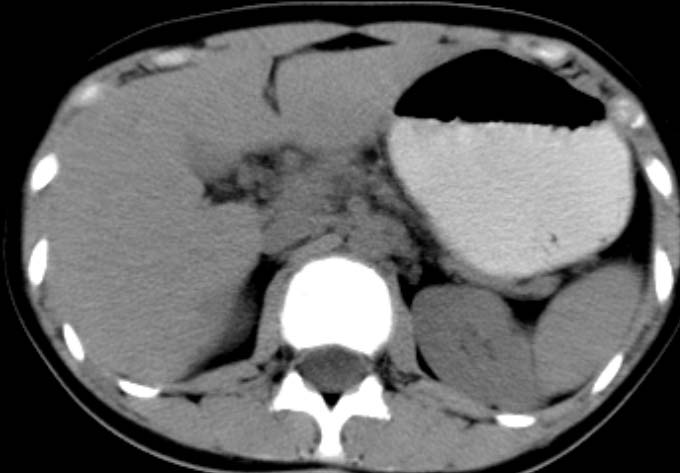

女,14岁。腹痛3天。腹部触诊未触及包块。碘剂阳性未增强。求助战友。。。。。。。。。。。

胰头部明显肿大,胰周间隙浸润,考虑胰腺炎可能性大

胰头部增大,周围模糊,有渗出,胰腺炎可能性大,建议结合化验检查;左侧输尿管上段略扩张.

胰头部明显肿大,胰头周脂肪密度加大。十二指肠环扩大受压。胰管未见确切扩张。考虑胰腺炎可能性大。建议增强扫描。

胰头部增大,周围结构模糊,并明显见渗出。支持:急性胰腺炎!

1)急性胰腺炎。2)肝右叶后上段肝内胆管结石。3)左侧输尿管上段扩张,原因待查。

胰头明显增大,周围结构不清,诊断胰腺炎的话,结合血或尿淀粉酶诊断比较明确了。

胰头部明显增大,胰管未见明显扩张,周围肠系膜血管显示清楚,胰头周围明显见渗出,还是考虑胰腺炎

胰头部明显肿大,胰周间隙浸润,胰管略增宽支持;胰腺炎诊断。

胰头明显肿大呈肿物样,周围脂肪密度增高,结合病人年龄及临床表现,首先考虑炎性改变,建议结合实验室检查明确。必要是复查或mr检查

病灶应在胰头下区,不一定是胰头,结合周边低密度水肿,是否可能为十二指肠(xi)室炎症或其它炎症。

胰周无明显渗出,吉氏筋膜未见增厚。血尿试验室检查不支持。排除胰腺炎。